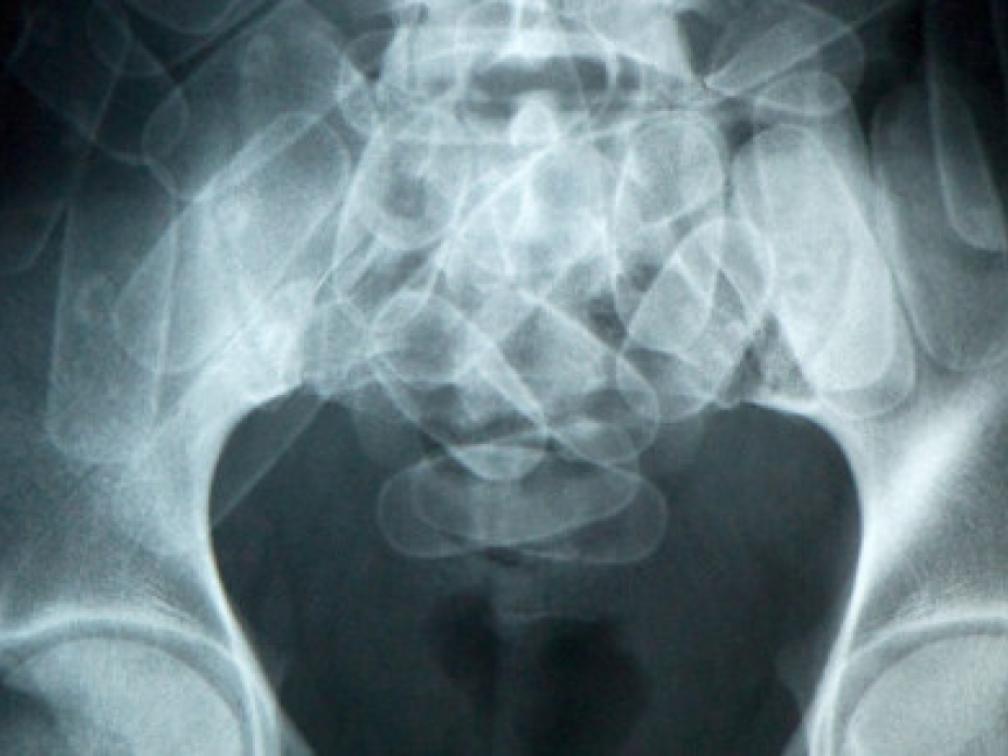

WILLEMSTAD — Curaçao heeft een nieuwe speciale (minder stralen) bodyscan van het merk Siemens aangeschaft om bolletjesslikkers op te sporen bij de luchthaven. De lokale autoriteiten zullen trainingen en informatie over het apparaat krijgen van Nederlandse experts. Dit is één van de vele maatregelen die getroffen worden om het aantal bolletjesslikkers dat drugs naar het buitenland vervoert, terug te dringen. Dat laat zowel de politie als de douane weten.

De huidige bodyscan werkt wel, maar niet 100 procent. Het apparaat mag van een radioloog nog gebruikt worden. De politietop voert regelmatig uitvoerige gesprekken met deze radioloog, die het apparaat controleert. Het is aan service toe, blijkt uit die controles. Dat kost echter veel geld en dus is ervoor gekozen om een nieuwe aan te schaffen in Nederland.

Het is nog niet helemaal duidelijk wanneer de nieuwe scan bij de luchthaven wordt geplaatst, maar dat zal hoe dan ook niet erg lang duren. Lid van het managementteam van het politiekorps KPC, Raymond Ellis: “Er zijn afspraken gemaakt met Nederland over de betaling hiervan en zodra het geld op hun rekening is gestort, krijgen wij de bodyscan toegestuurd.” Ellis schat dat het apparaat binnen zes weken na betaling operationeel zal zijn bij de luchthaven.